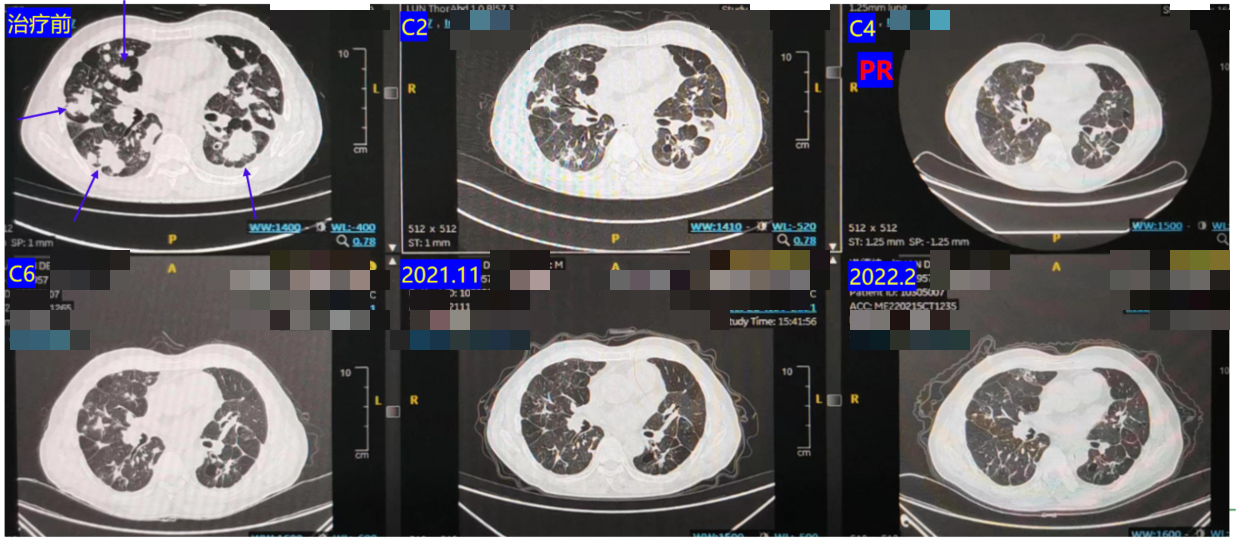

2021.04-2021.08:患者入组临床研究,接受信迪利单抗 + 西达本胺 + IBI305 治疗6周期。

复查CT显示肺部多发转移灶明显缩小,疗效评价为部分缓解(PR)(图8)。

2021.12-2023.12:调整方案为 西达本胺 + 贝伐珠单抗 维持治疗,进行16周期。

长期随访CT显示,肺部病灶持续维持在低水平,疗效评价持续PR。